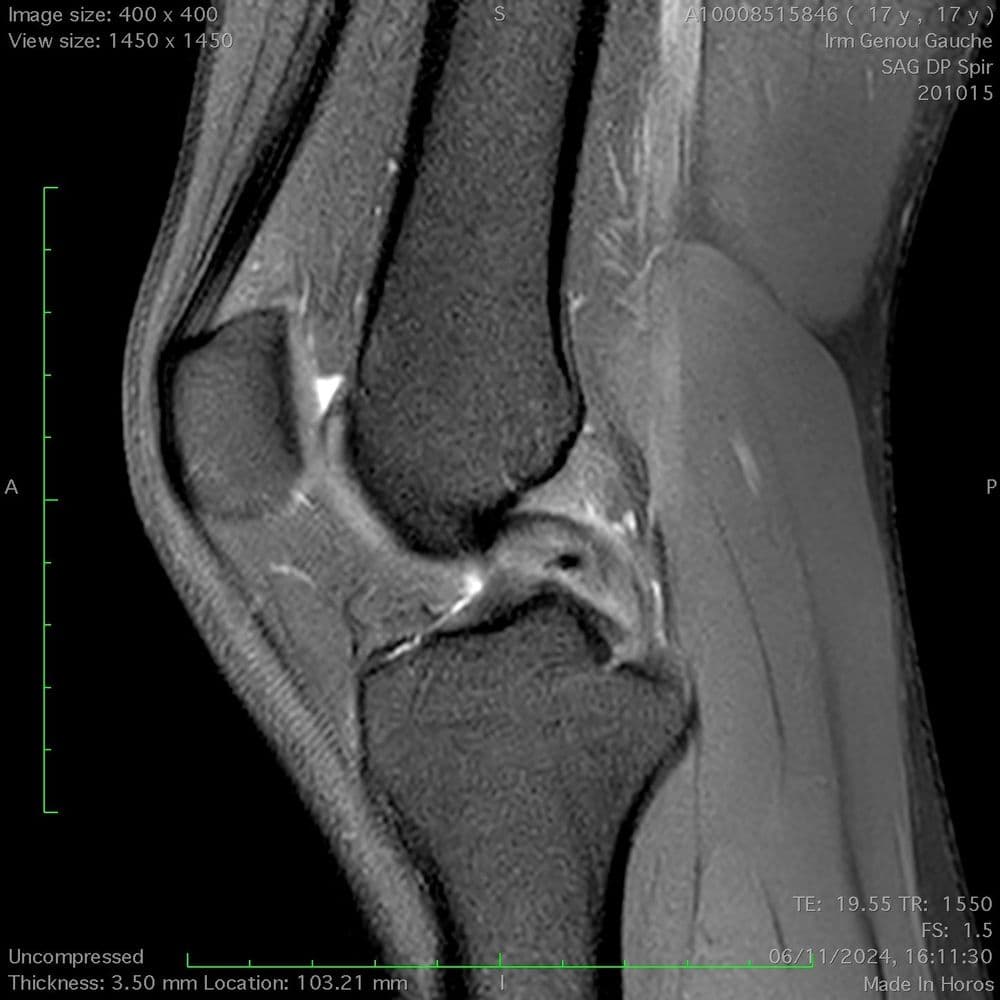

Rupture partielle du ligament croisé antérieur aux dépens du faisceau antéro-médial, avec aspect continu du faisceau postéro-latéral.

MRI